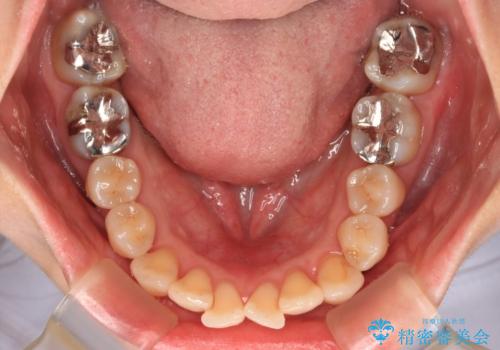

矯正治療後には奥歯の銀歯やむし歯をセラミックやゴールドにて治療を行い、大変整った口腔環境へと改善さ。れました